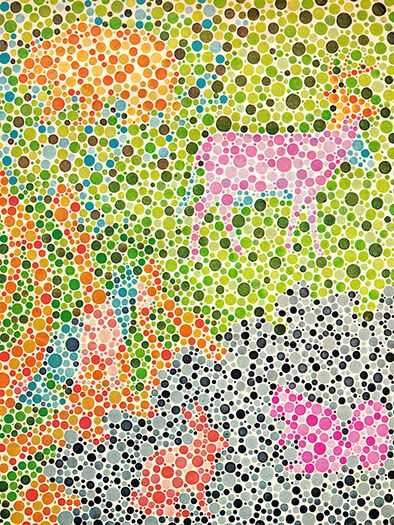

Daltonizam ili djelomična sljepoća na boje najčešće se može dijagnosticirati već u djetinjstvu. Postoje testovi kojima se utvrđuje percepcija boja i razlikovanje nijansi. Te testove čine grupe različito obojanih točkica koje formiraju neki oblik, provodi oftalmolog.